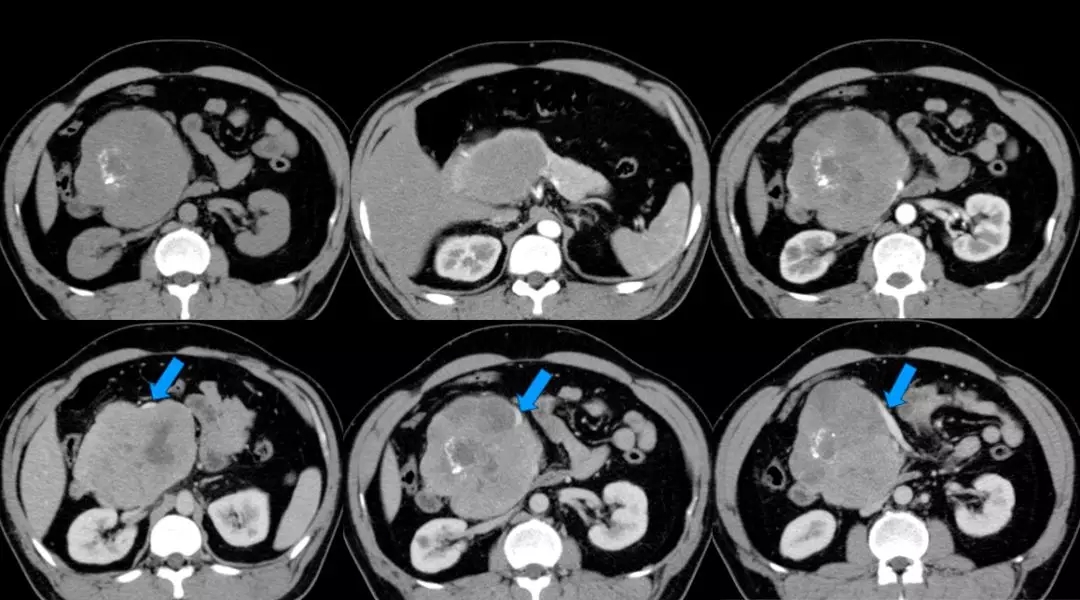

上腹部增强CT:胰头颈体积增大、胰头、颈部可见巨大软组织肿块影,长径约12 cm,与周围分界不清,其内密度不均匀,见片状低密度影及点片状致密影,增强扫描呈不均匀强化,病灶较胰腺实质强化幅度低,其内可见无强化坏死区。腹腔见数个小淋巴结影。脾周可见软组织密度影,长径约1.8 cm,强化方式与脾脏一致。双肾可见多个囊状无强化低密度影。左肺上叶可见斑片状密度增高影,增强可见明显强化。考虑:(1)胰头颈占位,考虑恶性;(2)副脾;(3)双肾多发囊状;(4)左上肺病变,炎症可能。(蓝色箭头为受侵PV-SMV)

数字化血管三维成像:(1)胰腺头颈部及相邻体部囊实性肿瘤,考虑实性假乳头状瘤可能大,相邻血管及十二指肠明显受压,门静脉主干旁个别淋巴结肿大;(2)副脾;(3)双肾多发囊肿